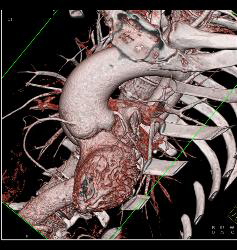

Dilated Aortic Root With Normal Origin of Coronary Arteries. Patient Had Marfan Syndrome and A Bicuspid Valve.